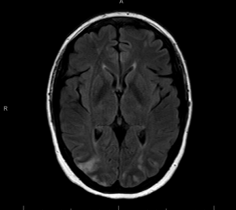

Case Presentation: A 46-year-old female with history of rheumatoid arthritis and asthma presented with chest and back pain to an outside facility and was evaluated for acute coronary syndrome and cholecystitis. Patient’s absolute eosinophil count (AEC) was 1.76 at that time. Patient was re-admitted with altered mental status and vomiting. Her AEC was 41. Strongyloides IgG titer was positive, but EGD showed no strongyloidiasis. Other infectious work up was negative. TTE showed pericardial effusion, CTA was negative for PE, and brain MRI showed embolic infarcts. A bone marrow biopsy showed increased eosinophils only. Patient was then transferred for higher level of care. Upon arrival, patient was ill-appearing, afebrile, tachycardic, normotensive with mild hypoxia and multiple ecchymosis. Physical exam was otherwise unremarkable. Labs showed WBC 28.6, AEC of 8.85, normal BUN/Cr ratio, Alk Phos 444, AST/ALT 45/70, INR 1.4, CRP 36, GGTP 507, troponin 431, PR3 >8.0, MPO .2, elevated strongyloides IgG antibody, decreased C4 and C3 complement, and normal total IgE. Antiphospholipid syndrome work up, cancer cytogenetics, fungitell, protein electrophoresis, cyclic citrullinated peptide, rheumatoid factor, blood cultures and stool parasites were normal. Skin biopsy showed vascular thrombosis, not vasculitis. CT Head/MRI/MRA Brain showed a watershed infarcts. TTE showed an EF at 61%, moderate pericardial effusion, patent PFO, SVC vegetations vs. thrombus, and thick mural echogenicity compatible with Loeffler’s endocarditis. Cardiac MRI showed extensive thrombi. Repeated CTH showed hemorrhagic conversion. Patient was treated with steroids, hydroxyurea, albendazole, and meprolizumab. Patient passed despite wide variety of aggressive treatment.